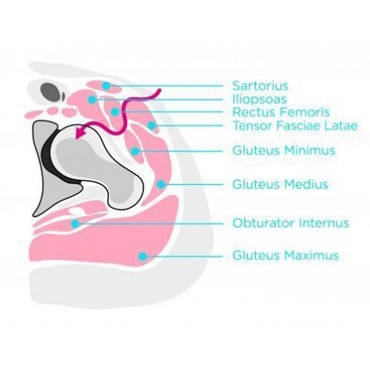

Minimal invazív csípőprotézis beültetés

Minimal invazív esettanulmány Pácienseink életének megváltoztatására összpontosítva, praxisunkban kizárólag a leginnovatívabb és legkíméletesebb eljárásokat alkalmazzuk. Ebben az esettanulmányban megismerheti Pétert, aki számára a Csípőprotézis Beültetés nem csupán egy műtét volt, hanem az új élet kezdetének kulcsa. A kiindulópont: megoldás a csípőfájdalomra Péter hosszú éveken keresztül küzdött csípőfájdalommal, amely korlátozta mindennapi tevékenységeit és életminőségét. Különböző kezeléseken […]